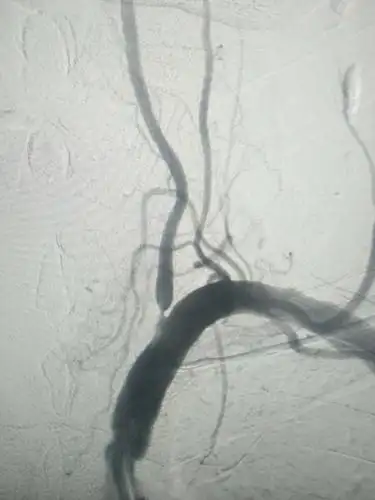

左侧椎动脉起始处重度狭窄